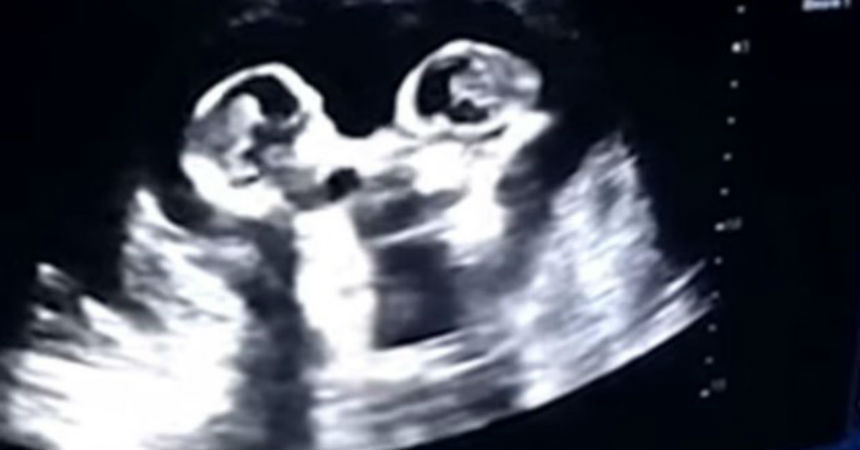

Los bebés suelen dar patadas mientras se encuentran en el útero de la madre, lo que no es ninguna novedad. Pero ahora una ecografía ha captado la tierna «pelea» entre dos gemelas a las que todavía le faltan varias semanas para nacer.

Una embarazada de cuatro meses se realizó una ecografía, en un centro de salud ubicado en la ciudad china de Yinchuan. Todo transcurría con normalidad hasta que su marido, que filmaba el monitor con el que se realizaba el control rutinario, descubrió que -a juzgar por sus movimientos- sus gemelas «parecían estar peleándose».

Tao, el padre de las bebés, explicó al periódico chino The Paper que le parecía muy divertido ver «una pelea de ellas como si estuvieran en un ring de boxeo».

El padre de la gemelas, relató que durante otra ecografía ambas parecían estar dándose un fuerte abrazo. Sin duda, serán unas niñas muy especiales, consigna 20 Minutos.

La particular escena se produjo a fines de 2018, y ahora que las niñas nacieron, el 8 de abril, ha sido ampliamente compartida en las redes sociales chinas.